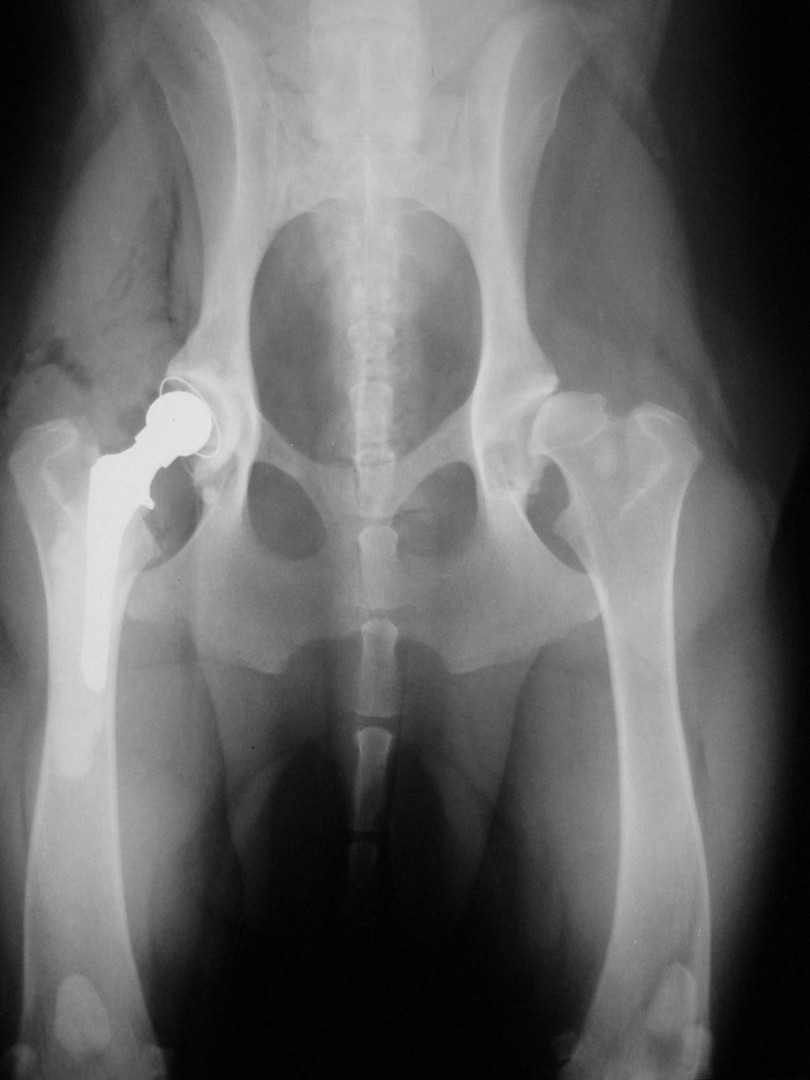

Bár a csípőízület megbetegedéseiről – mint a leggyakrabban tárgyalt ortopédiai megbetegedésről- első körben nem szerettem volna szólni, mégis megteszem, mert 2010. májusában egy hosszabb egyeztetést és szervezést követően beültettük az első teljes csípőízületi protézist…

A szervezés két részből állt: egyrészt felkerestük azt a magyarországi gyártót, aki a hazai anyagi lehetőségeket is figyelembe véve a szakmai szempontból is optimális rendszert le tudja gyártani, másrészt rábeszéltem Kendik Zsolt kollégámat, aki a hazai csípőízületi protézis beültetésének úttörője, hogy legyen segítségemre a műtét technikájának elsajátításában.

A tényleges műtét előtt temérdek teendő akad. A kutya teljes belgyógyászati kivizsgálása, egyéb ortopédiai és/vagy neurológiai betegségek kiszűrése, a tulajdonosokkal folytatott többszöri megbeszélés, a kockázatok mérlegelése és ezek részletes ismertetése jelentős energiát emészt fel. De ezek nélkül a beteg állat tulajdonosa nem tud reális döntést hozni: vállalható-e a műtét vagy sem?A műtéti időpont egyeztetése sem egyszerű: az operáció során 4 ember összehangolt munkájára, tökéletes aneszteziológiára és a műtétet követően az asszisztensek gondos munkájára van szükség a teljes gyógyuláshoz. Ez szintén jelentős szervezést igényel. A műtétet követő 10 napos kórházi ápolás és az ez utáni 3 hónapon át tartó szigorú mozgáskorlátozás betartása és betartatása a gyógyulás elengedhetetlen feltétele. Egy fiatal, ereje teljében lévő, energikus kutyánál ez néha nehezebb feladat, mint maga az operáció.

Az első műtét remekül sikerült és Connor, a skót juhász kutya megkapta a bal oldali új csípőízületét. A 7 napi kórházi tartás is problémamentesen zajlott és a varratszedés idejére a műtött végtag terhelése gyakorlatilag hibátlan volt. Az 1 hónapos és a 3 hónapos kontroll RTG vizsgálatokon sem jelentkezett szövődményre utaló jel, az 1 éves postoperatív időszakban már csak az látszott, hogy a műtött lábát jobban terheli, mint a nem operált végtagot. Így 2011. júniusában – immár sokadik csípőízületi protézis műtétként- a jobb oldali csípőízületét is megoperáltuk. Connor gyakorlatilag azóta teljes életet él és vidáman játszik társaival, még birkákat is terel…A majd két éves, a protetizálás során szerzett tapasztalatok azonban nálunk is hozzák a szakirodalomban leírt szövődményi lehetőségeket és arányokat. Leggyakrabban a beültetett protézis ficamával találkoztunk, de akadt sajnos kilökődési reakció is. Ezen problémák – az előzetes tájékoztatás ellenére is- mindig váratlanul érik a tulajdonost és az állatorvost egyaránt. Megoldásuk szinte kizárólag műtéti, ami újabb kockázatot, újabb fizikai és anyagi áldozatot jelent.